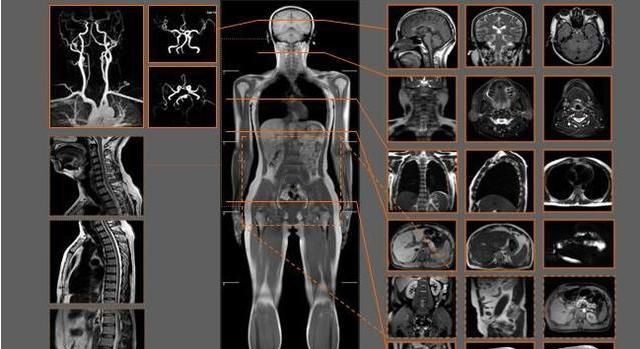

可以帮助我们清楚的看到人体中的异常,核磁共振的基本原理就是人体